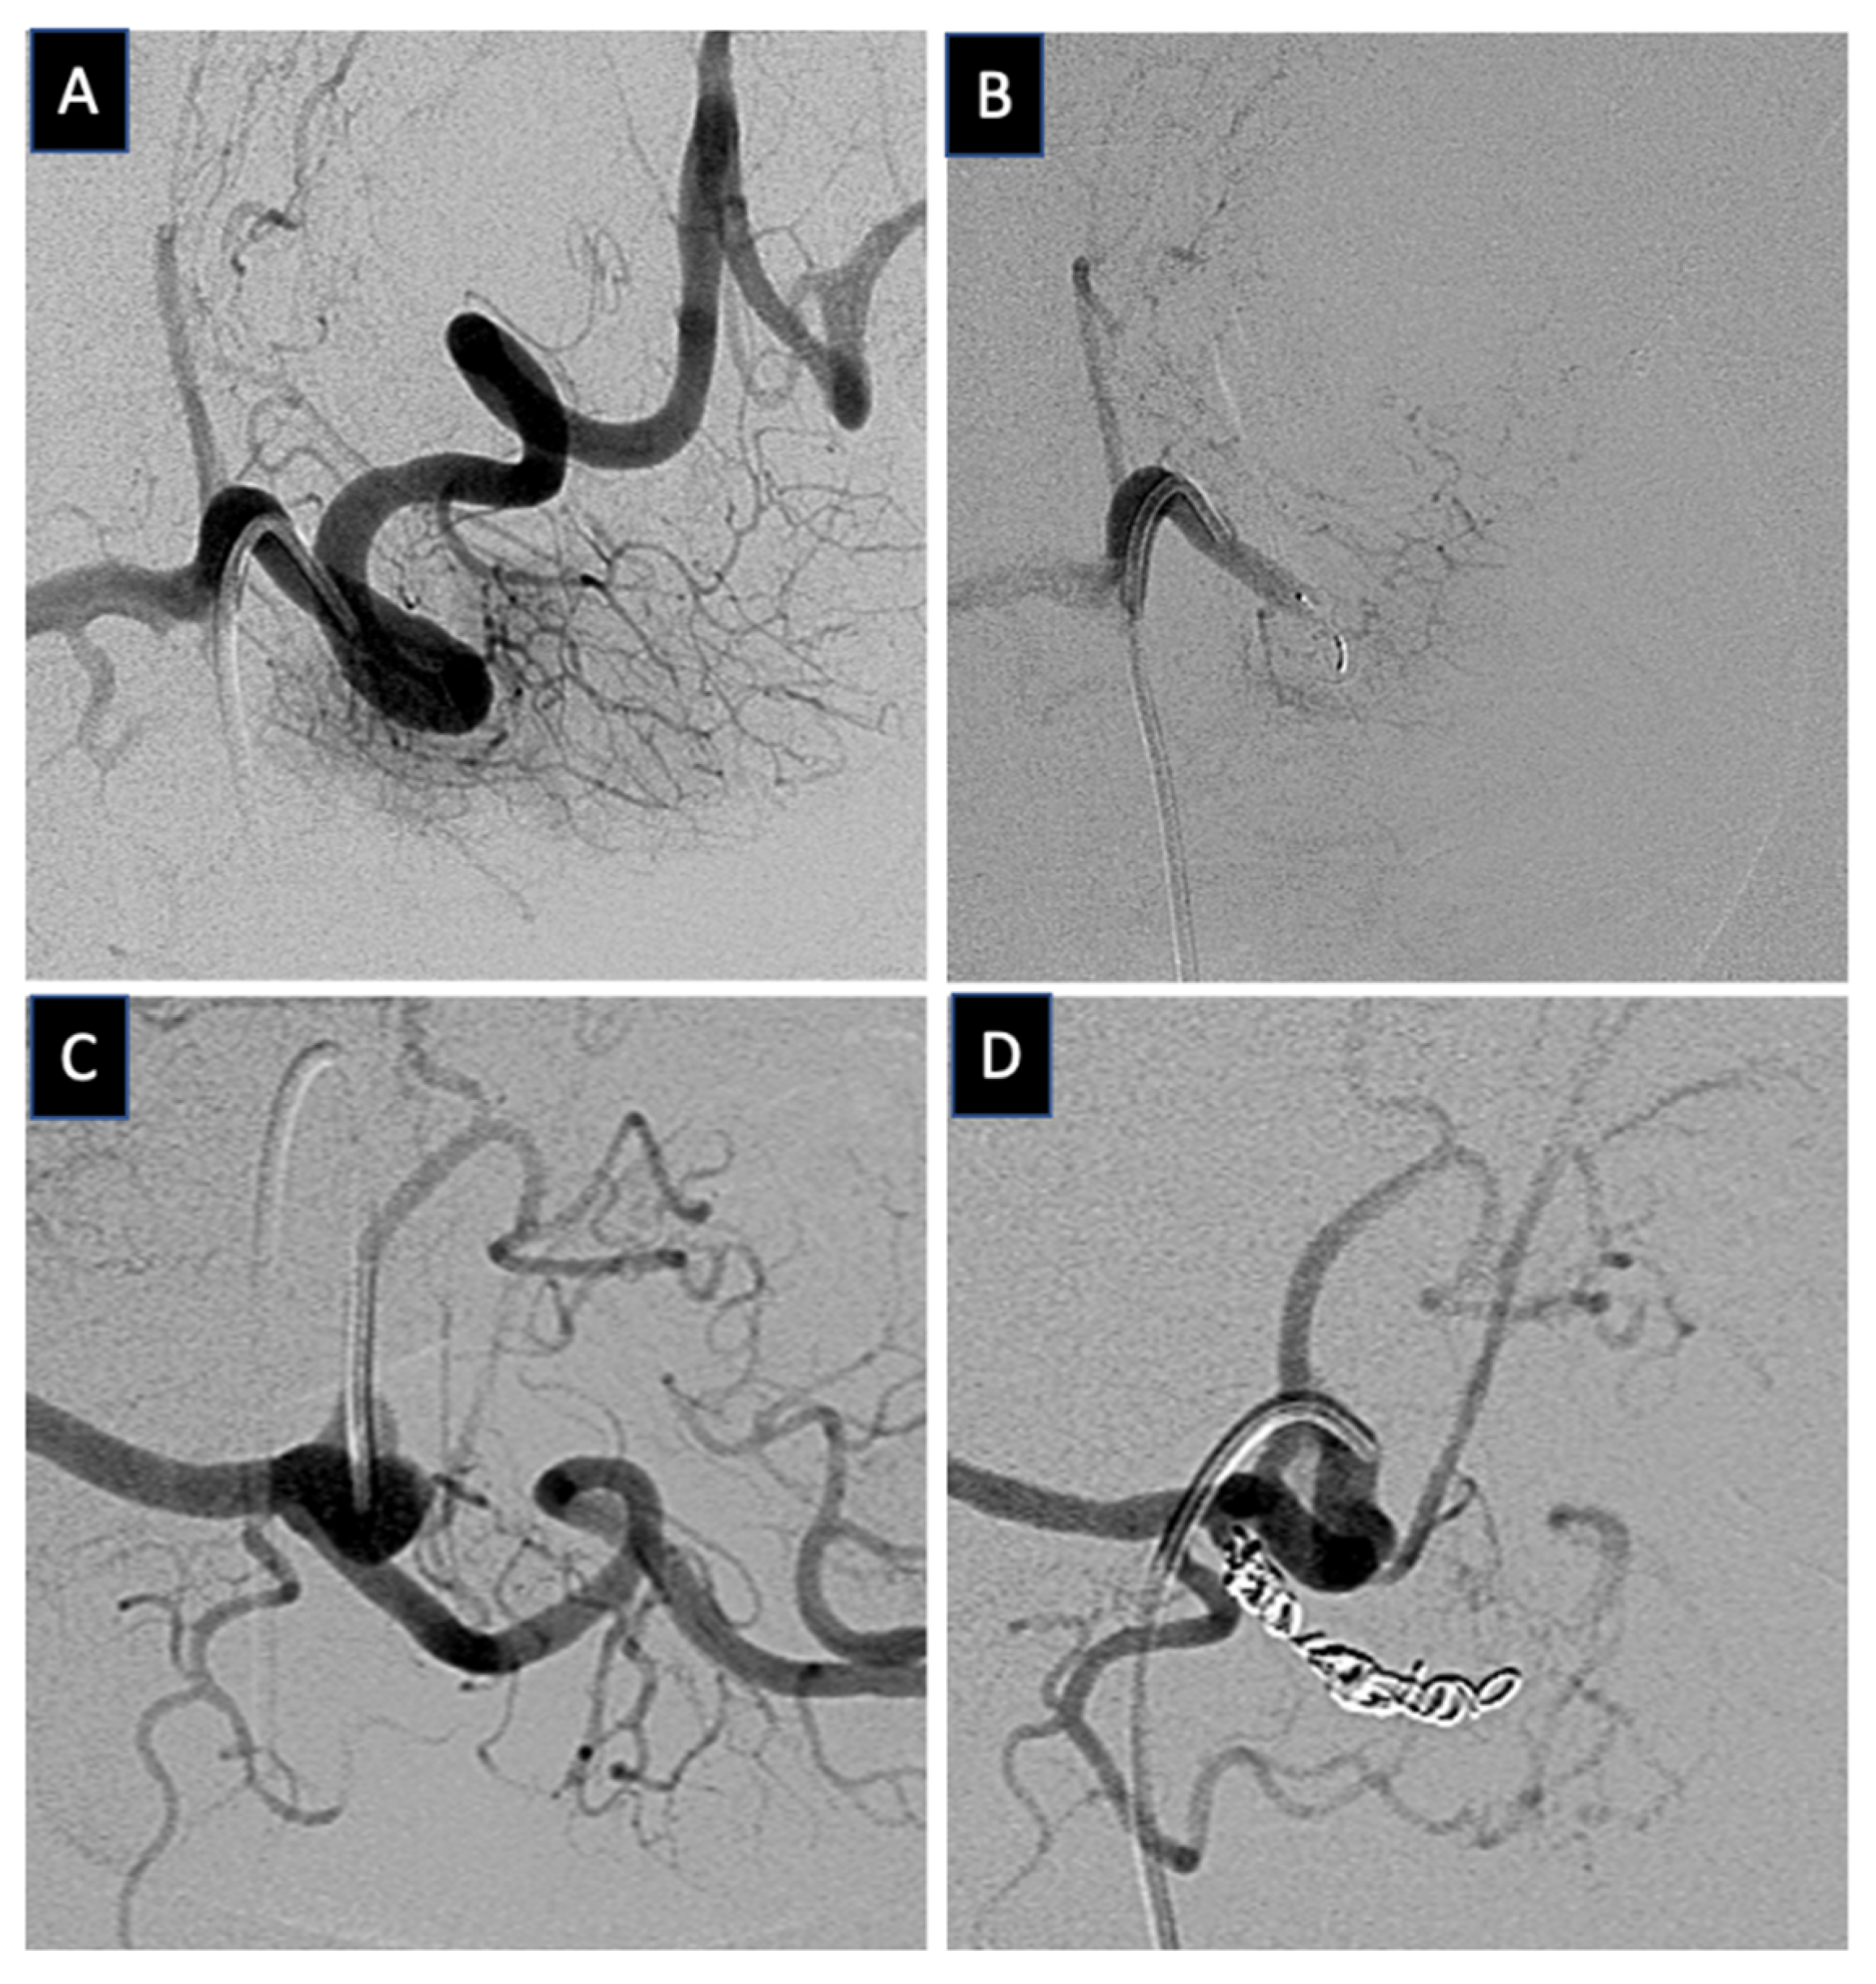

2.3. Technical Aspects